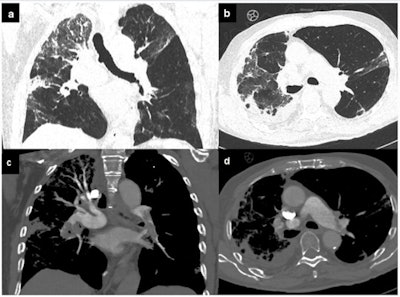

"A progressive shift from acute to chronic cardiovascular damage is not uncommon, even in apparently healed patients, and includes conditions like chronic thromboembolic pulmonary hypertension, recurrent arrhythmias, and progression to dilated cardiomyopathy. Accordingly, careful follow-up of these patients should be ordered in the convalescent stage," the authors recommended.

The researchers are keen to understand the role of imaging in the post-COVID-19 setting because they have seen that some apparently healed patients are potentially exposed to the sequelae of SARS-CoV2 disease, including dilated cardiomyopathy (particularly postmyocarditis), chronic heart failure, and postembolic pulmonary hypertension.